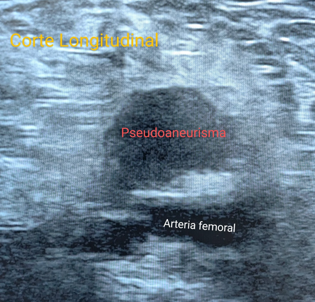

Imagen redondeada hipoecogénica y uniloculada de 25 mm x 12 mm de tamaño. Está conectada con la arteria principal lesionada a través de un cuello (en este caso con la arteria femoral derecha).

El Doppler ayuda a establecer el diagnóstico, ya que dentro de la lesión quística adyacente al vaso, se observa el signo de Yin Yang: flujo anterógrado y retrógrado en distintos colores, en la porción no trombosada.